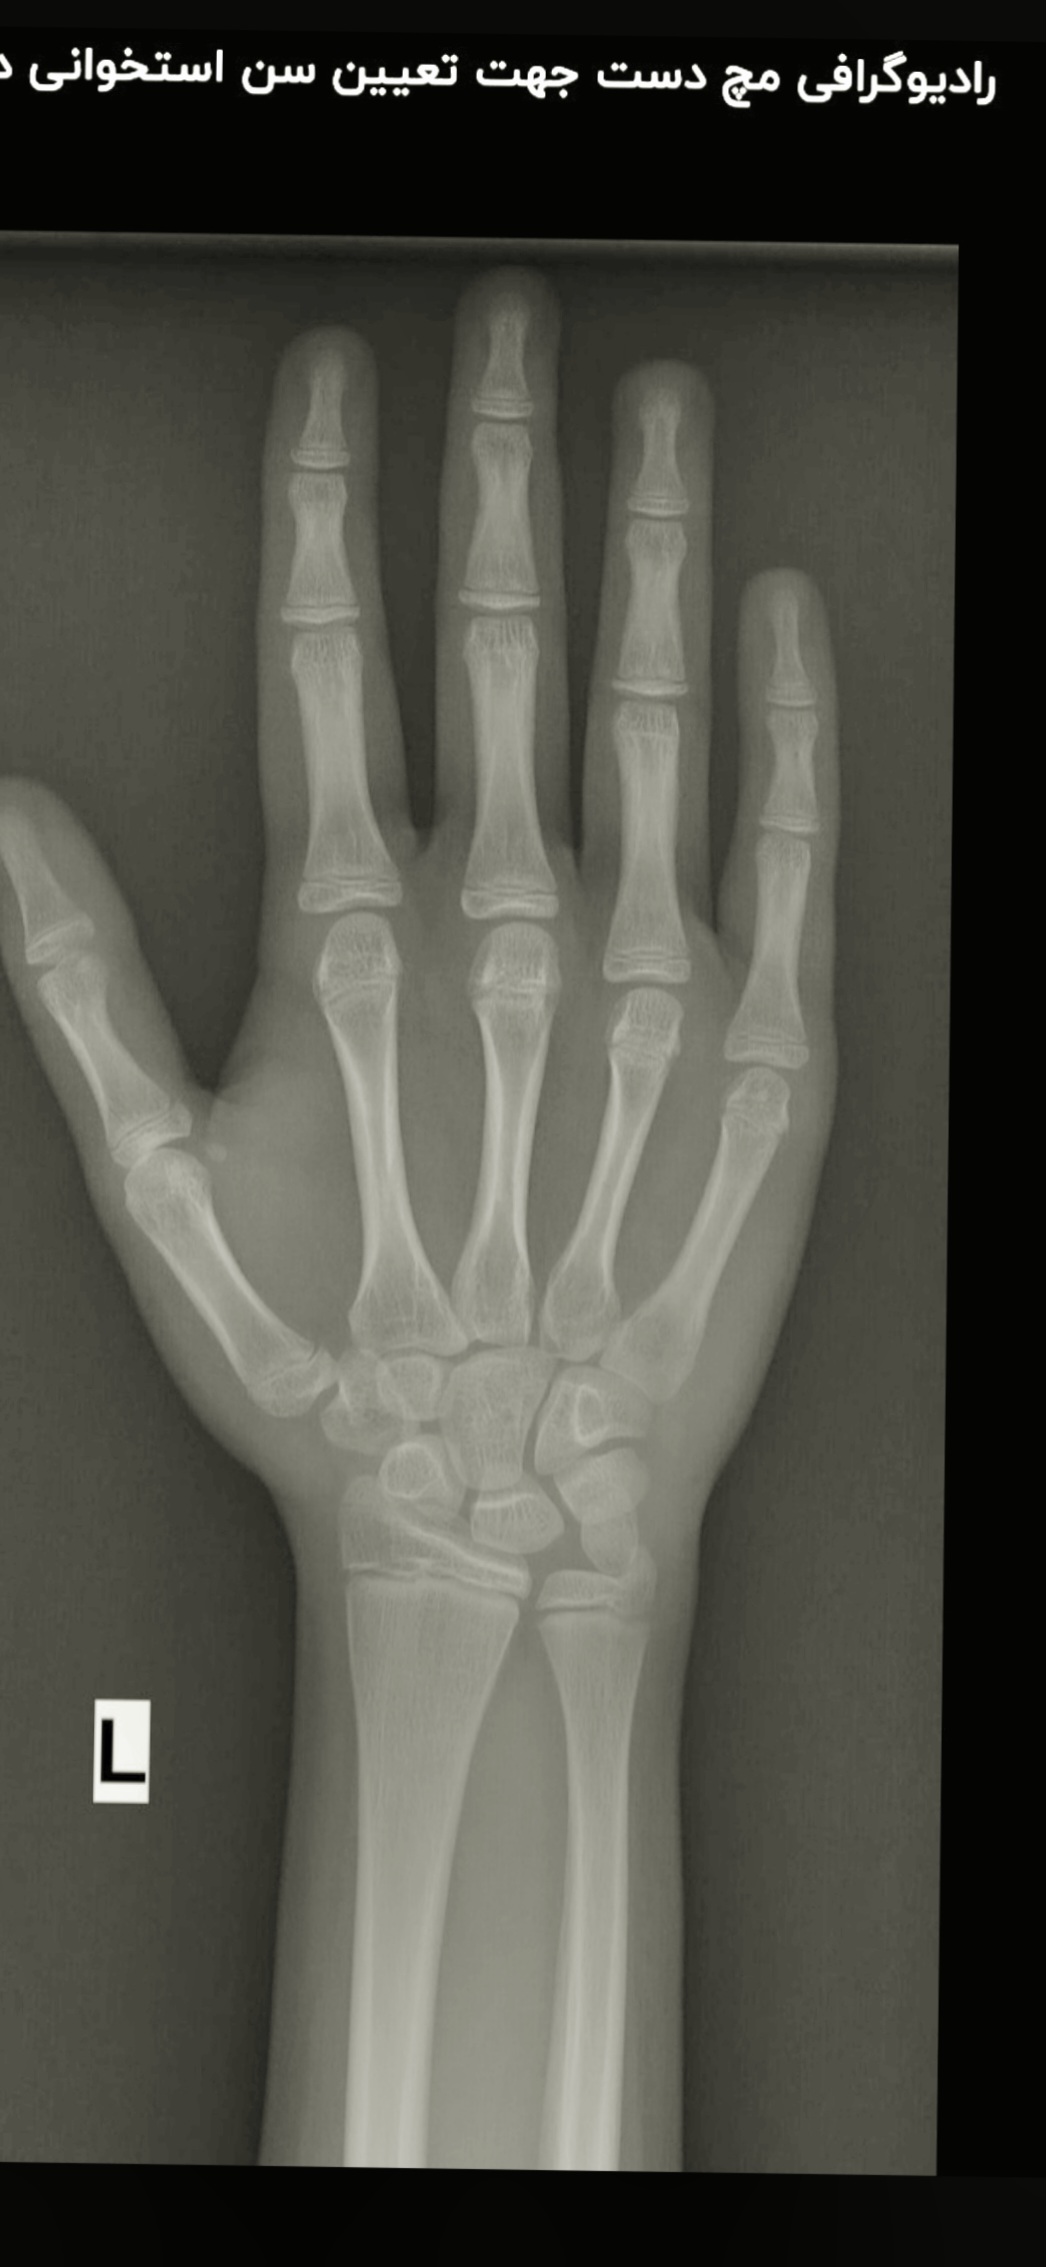

دکتر هم حدودی همین گفت از کجا فهمیدی؟

با خودم مقایسه اش کردم چند تا عکس مختلف تو سن های متفاوت دیده بودم که با اون ها هم مقایسه اش کردم تقریبا به این سن رسیدم

اسی این عکسو خود دکتر هم بلد نیست بخونه و طبق یه کتاب رفرنس ،مقایسه میکنه و جواب رو مینویسه‌ ...  اونم گاها اشتباه مینویسن.‌باید حتما طرف باتجربه و سن بالا باشه.

خودش ک نوشت 12سال البته عکس سه بعدی دیگه هم بود ک من اون نذاشتم.

برای پسر من با اون رفرنس نوشت۱۳. بردم دکتر باز رفرنس رو باز کرد گفت۱۳ و نیم هست